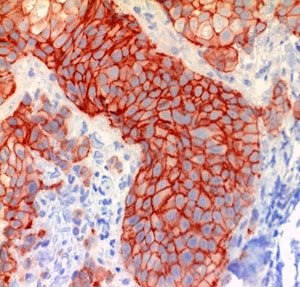

3. Immunhistochemie

Die immunhistochemischen Methoden basieren auf einer Antigen- Antikörper-Reaktion im histologischen Schnittpräparat, die mit geeigneten Färbesubstanzen sichtbar gemacht wird. Damit ist ein sehr spezifischer Nachweis von Gewebsantigenen möglich.

Wesentliche Einsatzgebiete sind

- Typisierung gutartiger und bösartiger Tumoren